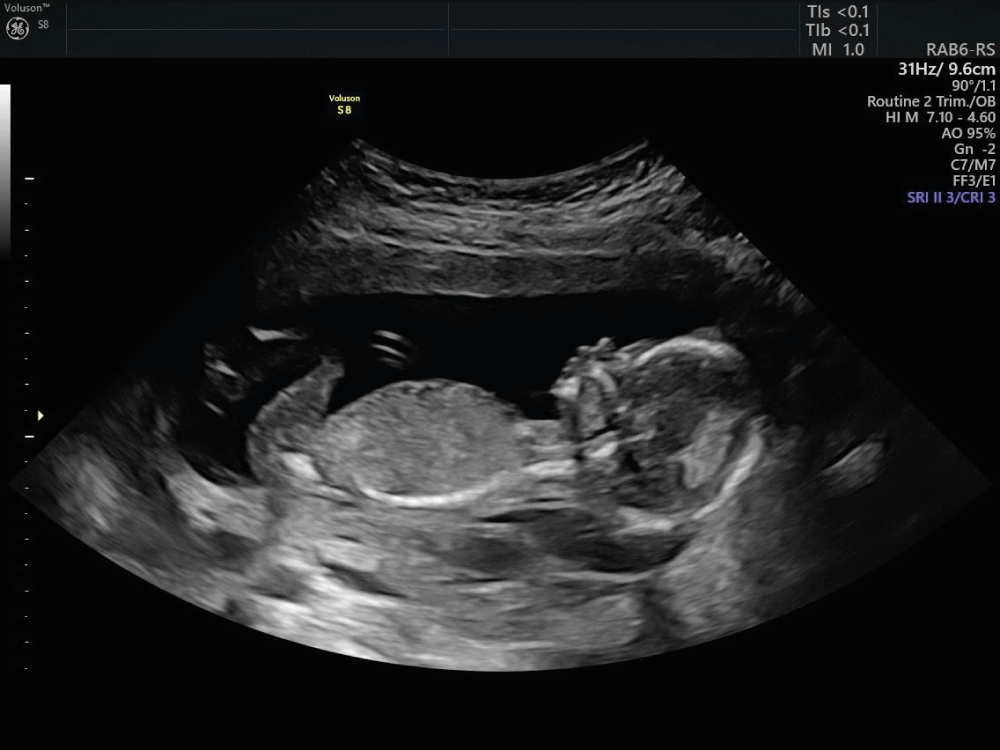

We provide quick and accurate Emergency Sonography, X-Ray, and Doppler services for immediate diagnosis.